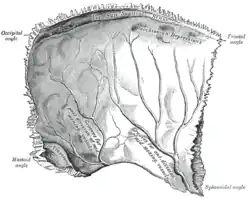

Left parietal bone. Inner surface.